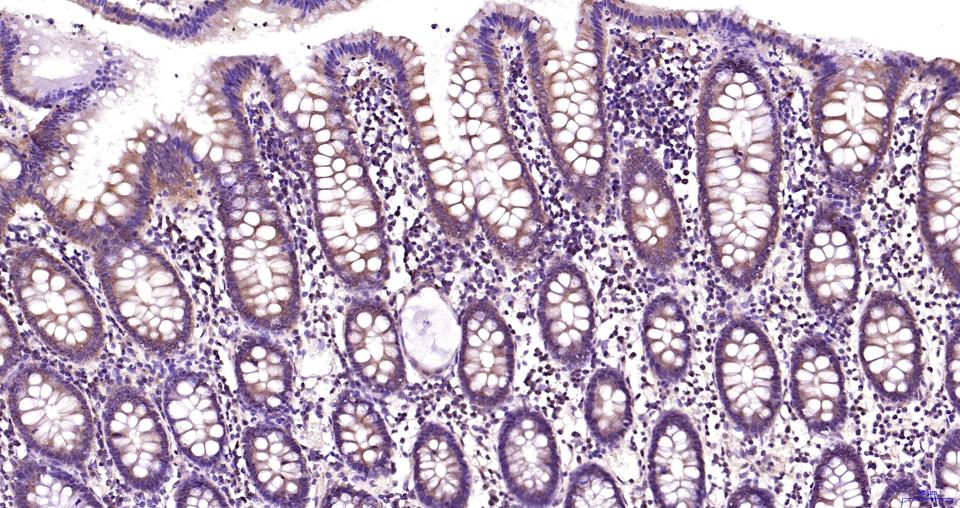

Paraformaldehyde-fixed, paraffin embedded Human colon; Antigen retrieval by boiling in sodium citrate buffer (pH6.0) for 15 min; Antibody incubation with MEK2 Monoclonal Antibody, Unconjugated (bsm-63042R) at 1:200 overnight at 4°C, followed by conjugation to the bs-0295G-HRP and DAB (C-0010) staining.